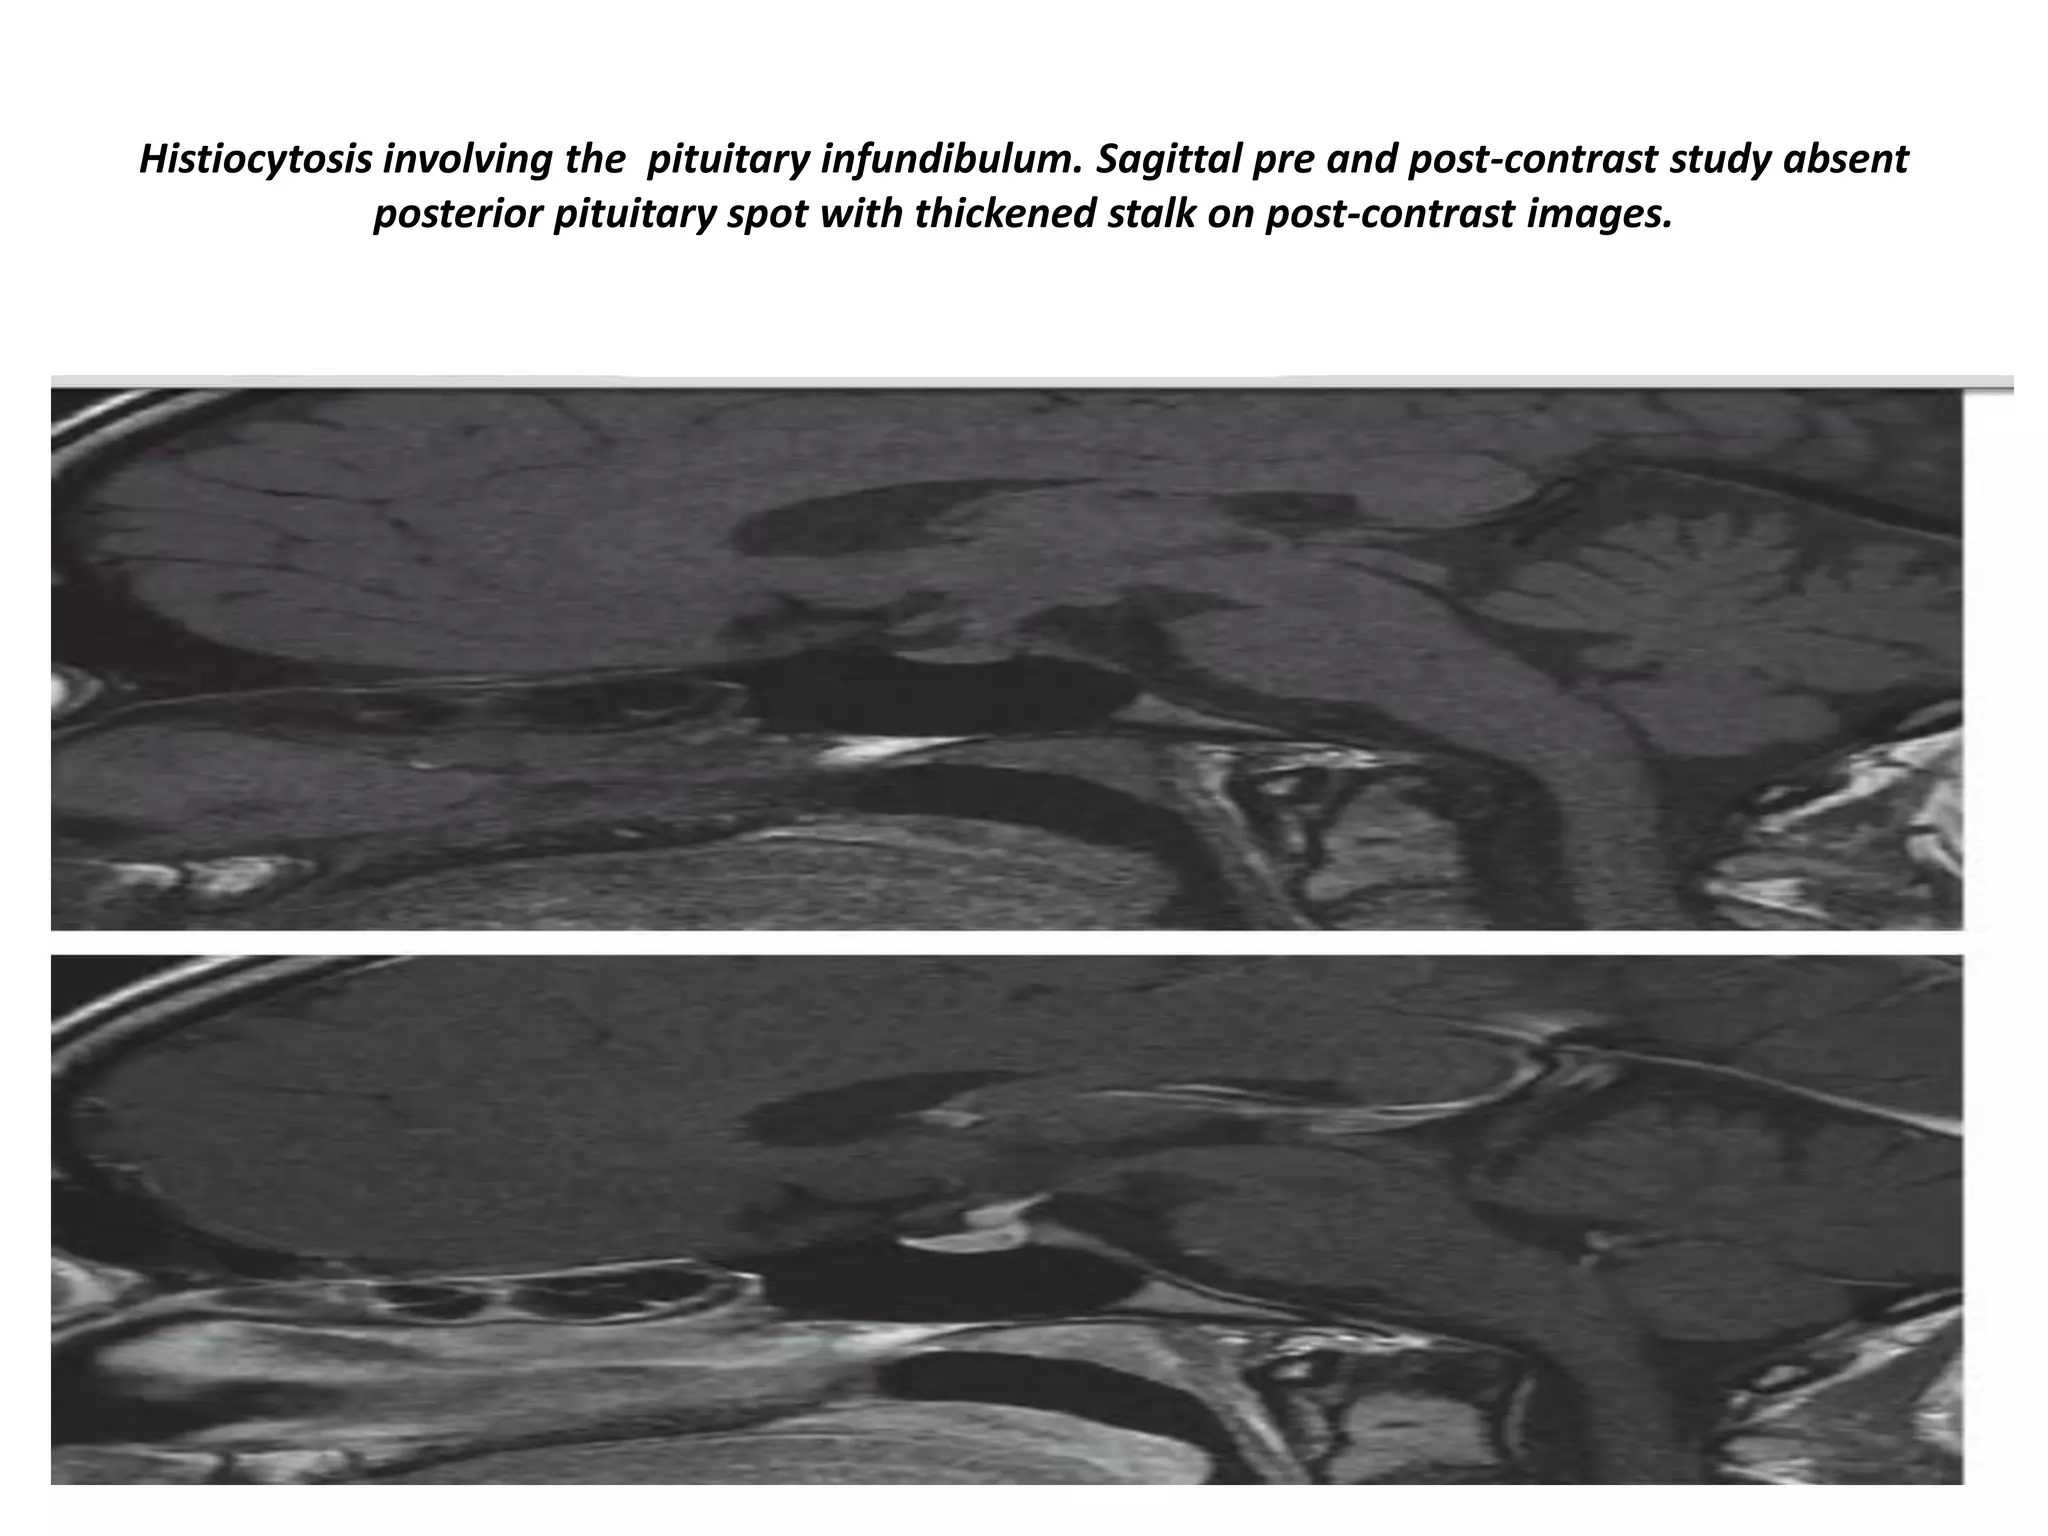

Histiocytosis involving the pituitary infundibulum. Sagittal pre and post-contrast study absent

posterior pituitary spot with thickened stalk on post-contrast images.